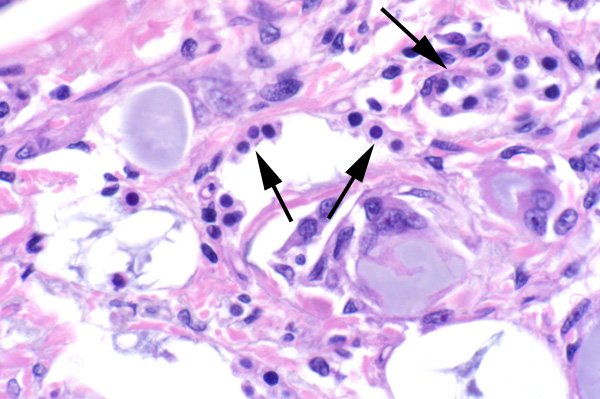

Multinucleated cells surround amorphous material. There is type II pneumocyte hyperplasia (arrows).